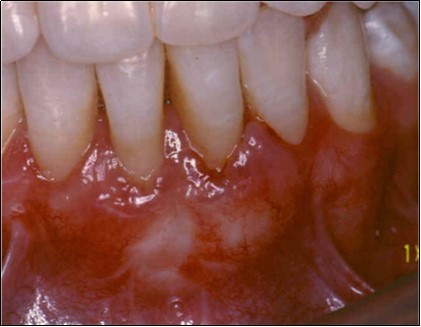

The patient under hard emotional stress that associated with bacterial plaque promoted ANUG with necrosis of alveolar bone and marginal gingival soft tissue in 31 and 41 (Figure 1). The patient was free of systemic disease and was not currently receiving any medication. Initial therapy was carried out using Er-YAG laser, to promote scaling and root planning and oral hygiene instruction. After initial therapy (Figure 2) the surgical method employed consists of the following steps as described by Langer and Langer5.

Figure 2.After initial therapy